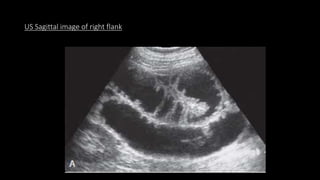

US Sagittal image of right flank